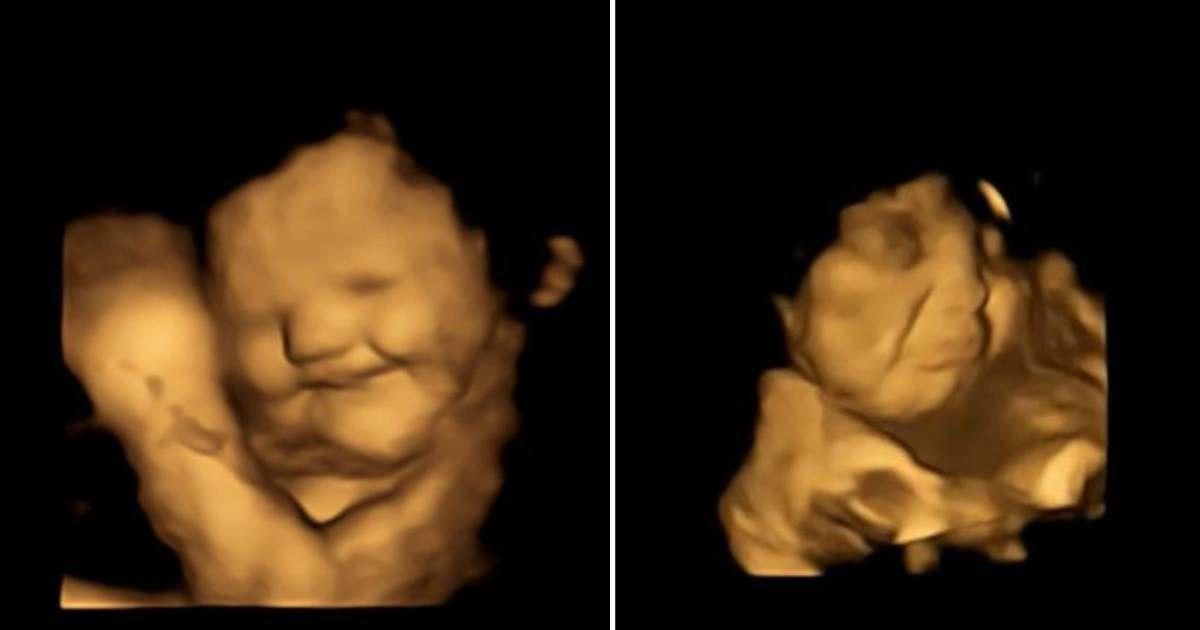

Here’s How Babies in the Womb Reacted to Pregnant Moms Eating Carrots and Kale

This is the first time researchers have captured the reactions of human fetuses when pregnant moms eat different food flavors.